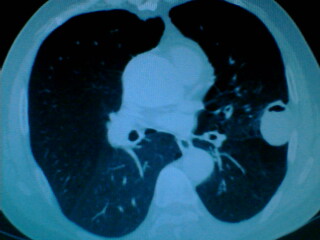

老年男性患者,右侧胸疼1月余(不是左侧),无其他症状

左肺外周类圆形病灶,其内低密度,可见液平及气影,周围肺文理见渗出样变,考虑左肺外周带肺脓肿。

左肺舌叶胸膜下卵圆形囊性肿块,内有液-气平面,邻近胸膜无增厚,没有肺窗,周围情况显示不清,考虑胸膜下肺囊肿并感染,病人年龄较大,有胸痛应警惕其他,但神经源性肿瘤暂不考虑。